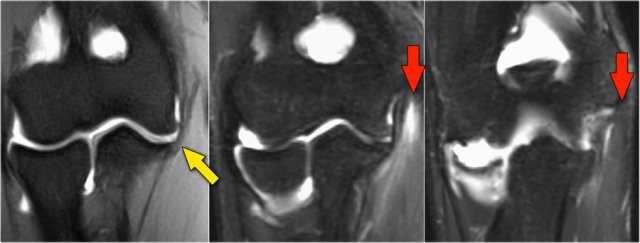

Coronal view:

1. Lateral collateral ligament is completely stripped (yellow arrow).

2. radial head is subluxed.

3. marrow edema of the coronoid process due to the fracture (red arrow).

Sagittal view:

1. Radial head is a little bit subluxed posteriorly (yellow arrow).

2. Large effusion and capsular disruption posteriorly.

3. Contusion of the posterior side of the capitellum as a result of impaction by the coronoid process (red arrow).

All these signs are the result of a posterior dislocation.